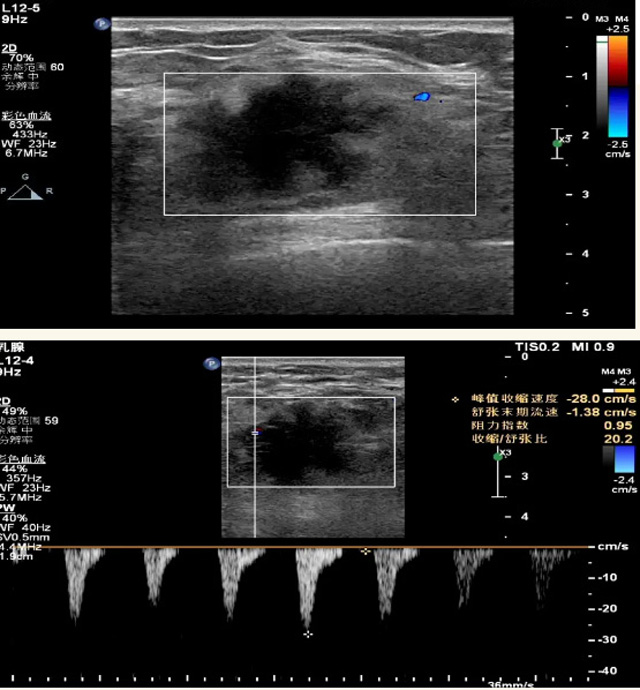

乳腺B超检查无辐射,对囊性病变敏感,可以实时观察病灶。超声引导活检跟手术前的定位。就是它对于微小的钙化查出率比钼靶稍微差点。磁共振MRI检查也是是没有辐射的,对备孕跟已经怀孕的人士比较友好。不用担心这个辐射影响胎儿问题。对乳腺病灶敏感性较高,致密乳腺病灶、乳腺癌的复发,准确鉴别囊性及实性病变。可以帮助临床医生判断恶性、良性病变。但是MRI磁共振对微小钙化不明显,微钙化还是钼靶靠谱点。检查时间比较长,有伪影的影响。费用相对B超,钼靶高很多。

乳腺B超